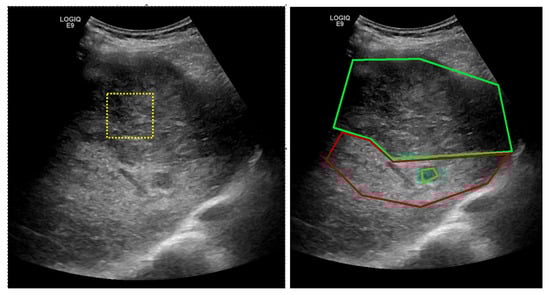

For training the proposed CNN model, the train dataset was augmented by means of rotation, zoom and reflection operations. Rotations in the range [−45 ,45 ], every 5 degrees, and zoom out/in with a factor of 0.8 and 1.2 were applied. A validation set was used for evaluating the classification performance during training. Table 2 shows the distribution of samples per class for training, for validation and for testing. Example images for each class in the two datasets are shown in Figure 3, Figure 4, Figure 5 and Figure 6.

Figure 3. HCC patches from dataset GE7.

Figure 4. PAR patches from dataset GE7.

Figure 5. HCC patches from dataset GE9.

Figure 6. PAR patches from dataset GE9.